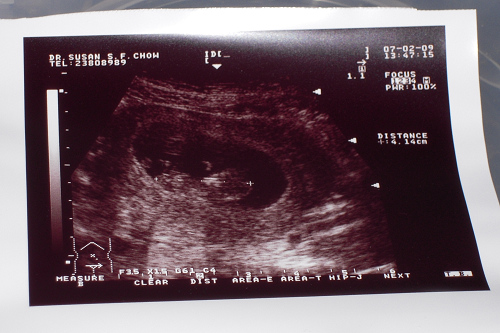

b朗快將升級成為哥哥,事緣朗爸和朗媽的造人計劃於趕工下再度成功,預產期為八月下旬;

朗爸一直留待至得知小b的性別後才為大家報喜,原先在月初朗媽於廣華醫院做結構性超聲波掃瞄檢查時,是有機會得悉小b的性別,但醫生說小b當時的位置使他看不清楚是男是女外,最重要是看不清楚心臟的結構,需要預約兩星期後再作檢查;

兩天前再往醫院檢查,這次醫生可清楚從掃瞄影像看到小b的心臟及肺部等結構,結果一切正常,而在我們要求下他說了「多數係男仔」;

小b的第一張掃瞄圖~